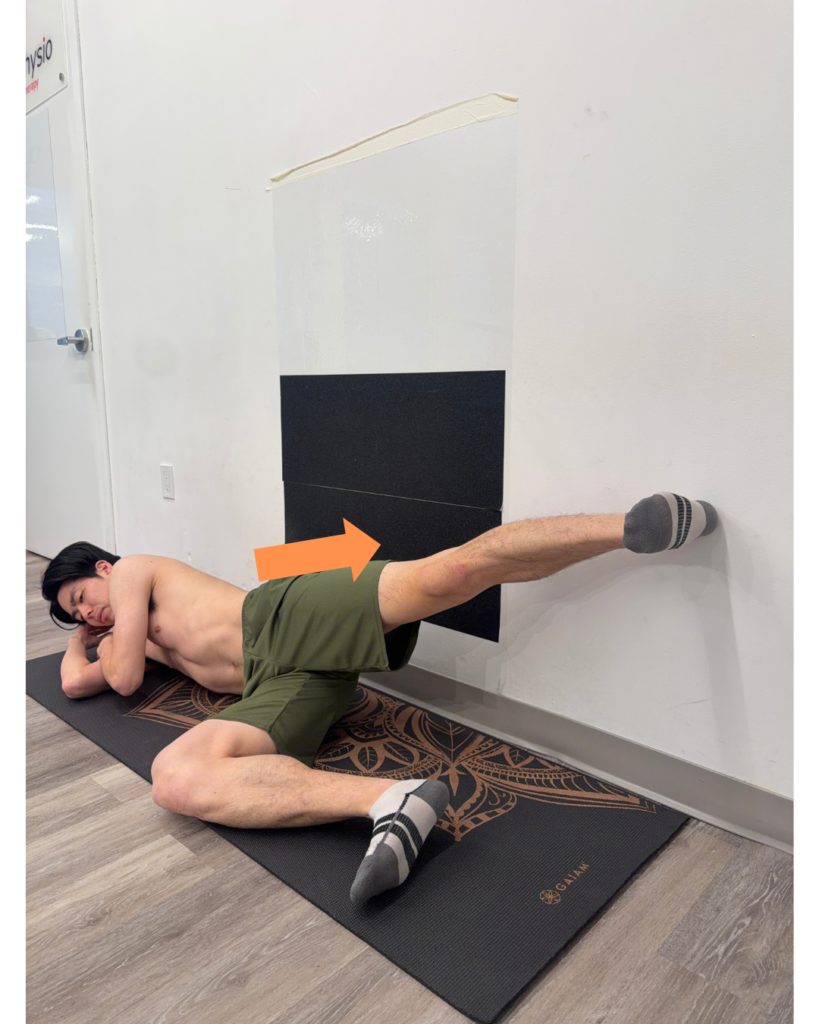

2. Posterior Depression Exercise: Side-Lying Wall Push

Goal: Improve stance stability and push-off

How to perform:

- Lie on your side facing away from a wall

- Place the heel on the wall

- Elongate your trunk(pelvic depression)

- Gently push into the wall

- Feel engagement in glutes and trunk

Focus:

- Prevent pelvic drop and decrease stress on the lower back

- Improve coordination with the opposite anterior elevation